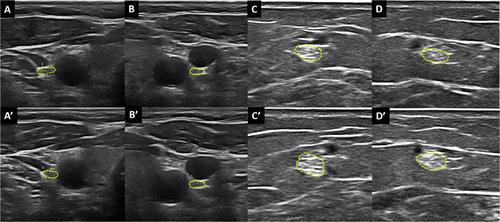

Abstract Image